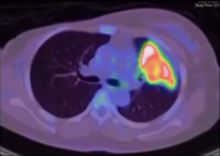

A 36-year-old woman was diagnosed with a left lung mass, which was incidentally detected during a routine x-ray examination. She had undergone right radical mastectomy with axillary clearance for carcinoma in July 2014. A thorax CT scan showed a large left upper lobe lung mass, with another nodule in the same lobe. A PET scan showed avid SUV take up in the left upper lobe primary mass, with multiple satellite lung nodules in the same lobe and ipsilateral mediastinal nodes. EBUS-guided biopsy revealed mucinous adenocarcinoma of the lung. In view of the Stage IIIA disease, she underwent two cycles of neoadjuvant chemotherapy with Cisplatin/Pemetrexed. Downstaging of the tumor was achieved. A repeat CT scan revealed a slightly smaller left upper lobe mass in continuity with the hilum. The mass abutted the mediastinum and narrowed the left upper lobe bronchus, with no mediastinal lymphadenopathy. In view of these findings, it was decided to proceed with definitive surgery.